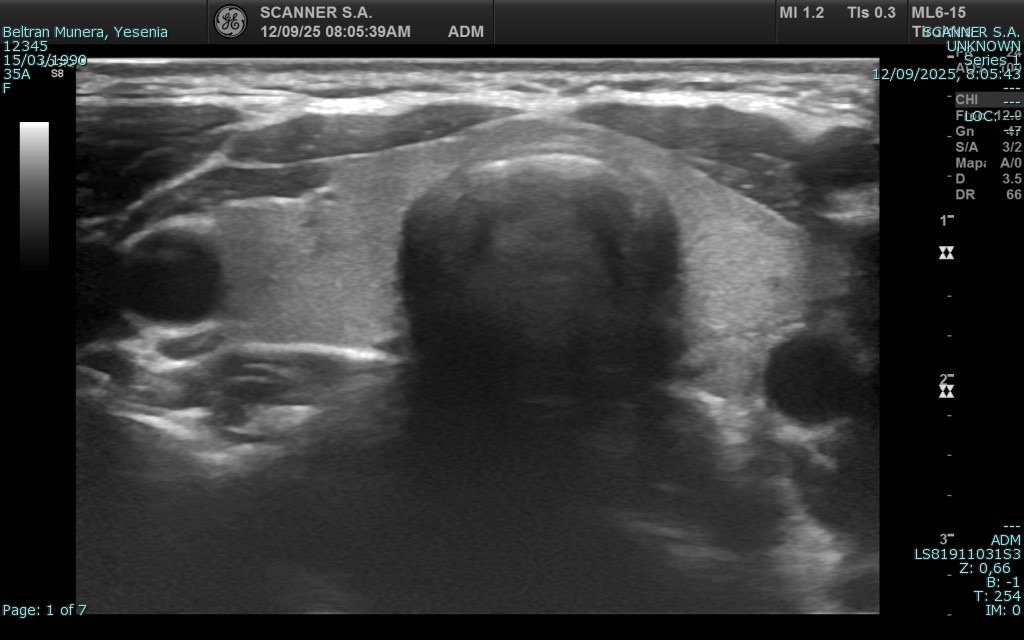

La ecografía es una técnica de diagnóstico por imagen no invasiva que utiliza ondas de ultrasonido para visualizar en tiempo real órganos, tejidos blandos y estructuras internas del cuerpo. A diferencia de otros estudios, no emplea radiación, lo que la convierte en una herramienta segura, ampliamente utilizada en diversas áreas médicas para detectar alteraciones, monitorear enfermedades y apoyar decisiones clínicas con agilidad y precisión.

En SCANNER S.A. contamos con equipos ecográficos de alta resolución, diseñados para ofrecer imágenes claras y detalladas. Nuestro servicio incluye tanto ecografía general como ecografía especializada, permitiendo realizar estudios abdominales, pélvicos, ginecológicos, obstétricos, renales, tiroideos, de partes blandas, musculoesqueléticos y más.